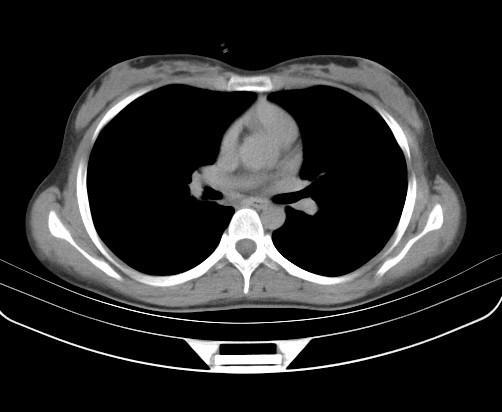

胸部